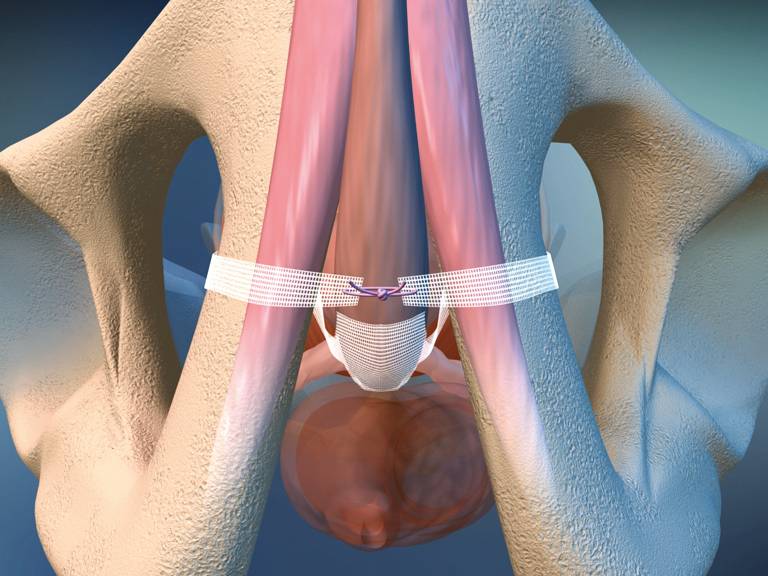

La uretromeatotomía es un procedimiento quirúrgico ambulatorio que se realiza para ampliar el meato uretral y el segmento distal de la uretra cuando existe una estrechez que dificulta la salida normal de la orina 🚻

🏥 ¿Cómo se realiza?

El objetivo es eliminar la obstrucción y restablecer un flujo urinario adecuado.

- 1902057: Uretrotomía interna endoscópica.

- 1902074: Uretroplastia.